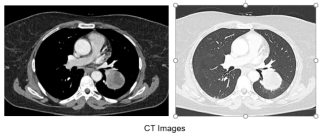

Case presentation

We report the case of a 17-year-old previously healthy male who developed sudden severe dyspnea while recreational skiing at a moderate altitude of 2'200 meters. On-site emergency management required immediate bilateral needle decompression, followed by urgent transfer to hospital care. Imaging confirmed a complete bilateral pneumothorax with bilateral apical subpleural blebs (Figure 1). Sequential bilateral chest tube placement was performed, and the patient subsequently underwent staged bilateral video-assisted thoracoscopic surgery with apical wedge resection and mechanical pleurodesis. Postoperative recovery was uneventful, with no recurrence during follow-up. Etiological investigations revealed normal alpha-1 antitrypsin levels. Transthoracic echocardiography identified a bicuspid aortic valve associated with moderate aortic regurgitation (grade 2/4). Combined clinical, radiological, and cardiac findings ultimately led to the diagnosis of Marfan syndrome, previously unrecognized.